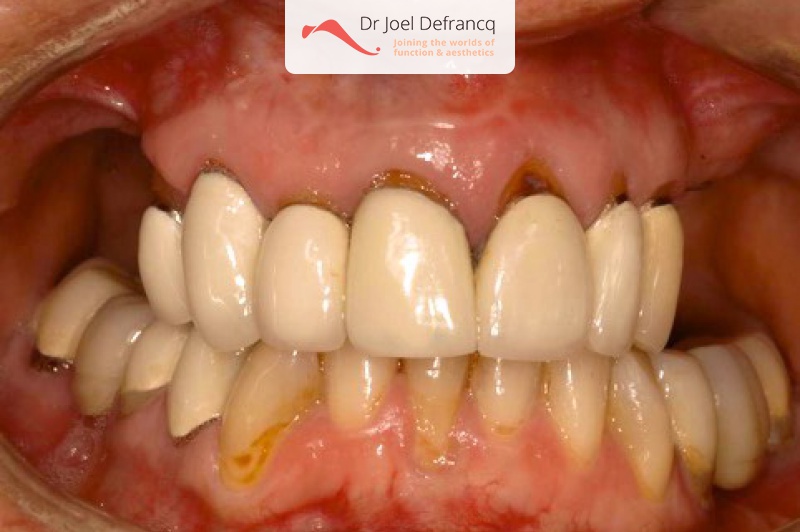

Esther: new teeth in a week - implants

Behandeling tandheelkundige implantaten

- Vaste tanden op implantaten (bovenkaak)

- Vaste tanden op implantaten (onderkaak)